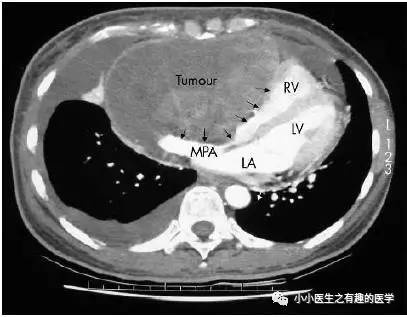

44岁女性,平素体健,进行性的呼吸困难3月,双侧踝周水肿。

A 44 year old woman, who had enjoyed good health up until recently, presented with a three month history of progressive shortness of breath and bilateral ankle oedema.

LV:左心室,不是LV包包。MPA:主肺动脉。

这个相对简单,是肺动脉严重受压了,引起类似充盈缺损的改变。

纵隔镜检查,病理:恶性梭形细胞肿瘤。

Mediastinoscopy and biopsy of the tumour was subsequently performed which yielded malignant spindle cell tumour by histology.